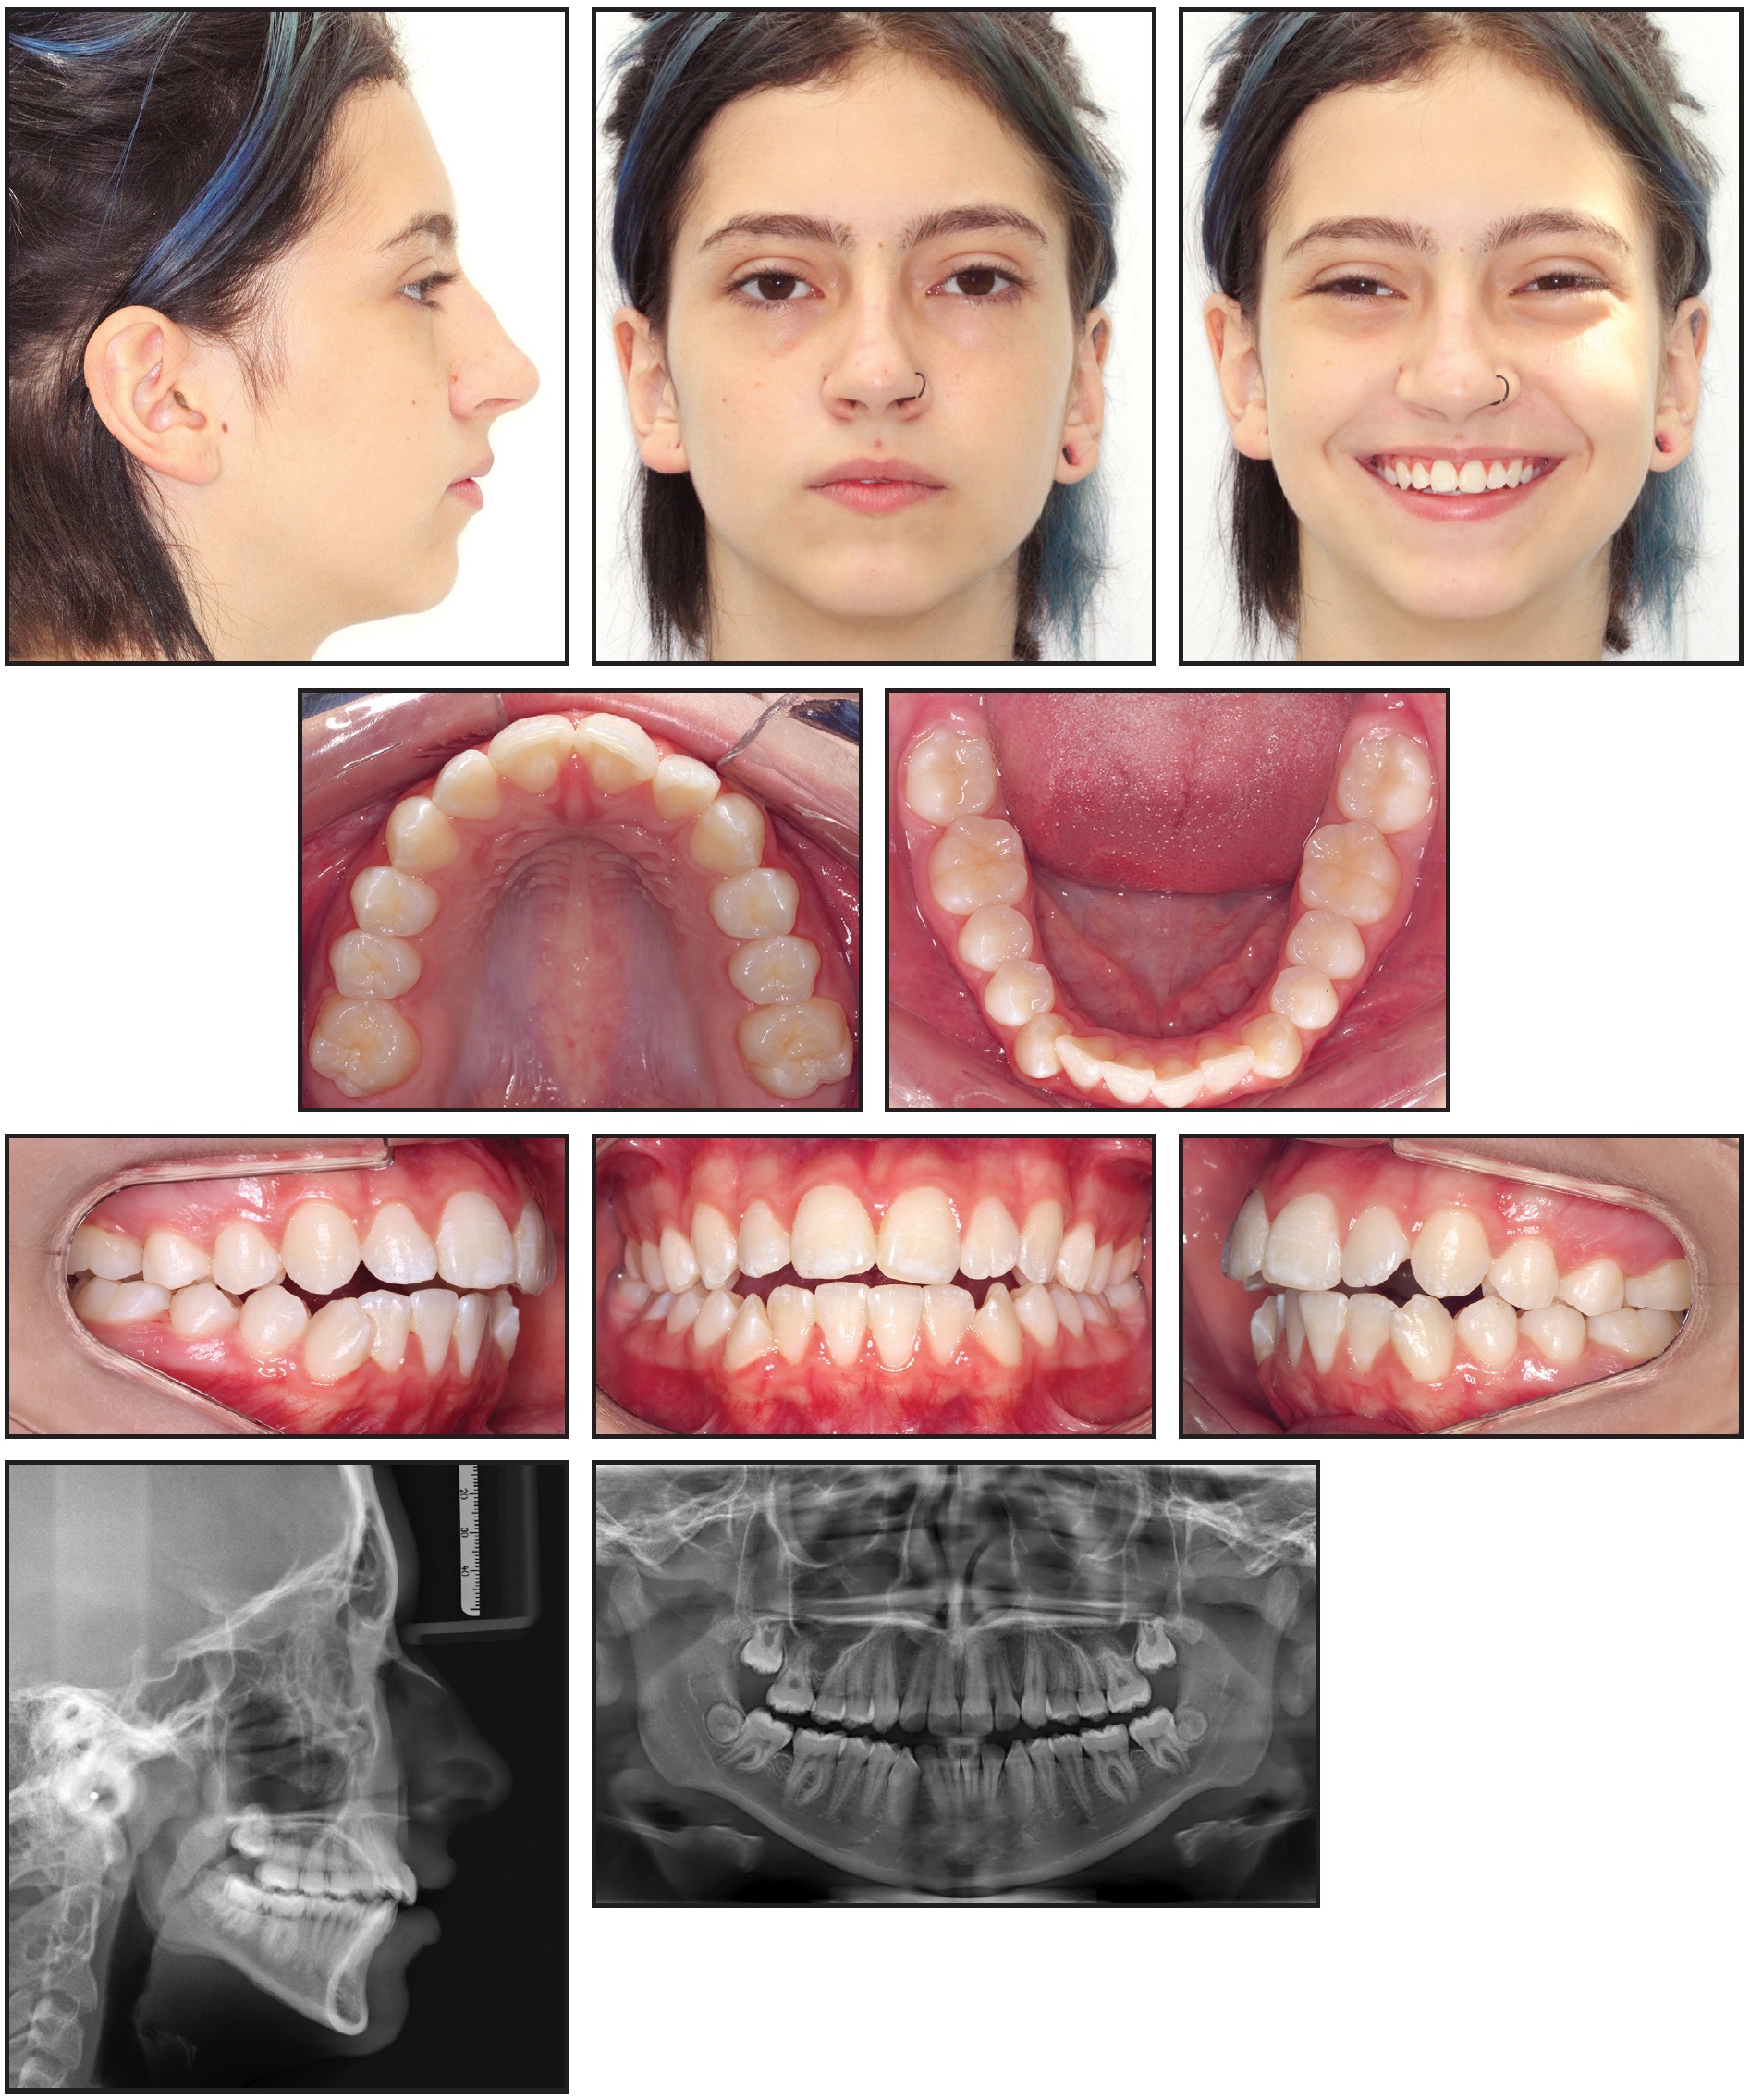

A 13-year-old female presented with the chief complaint of an anterior open bite (Fig. 6).

Fig. 6 13-year-old female patient with bilateral Class I molar relationship, anterior open bite, moderate lower anterior crowding, and excessive overjet before treatment (continued in next image).

Clinical examination confirmed an anterior open bite extending from first premolar to first premolar, a bilateral Class I molar relationship, moderate lower anterior crowding, and excessive overjet. The panoramic radiograph revealed the presence of unerupted upper second and lower third molars and agenesis of the upper third molars. The upper second molars were favorably positioned for later eruption,36 with incomplete rhizogenesis (Fig. 6B). There was no deviation between centric occlusion and centric relation, and there were no signs of TMD. Cephalometric analysis found an anteroposterior maxillomandibular discrepancy with mandibular deficiency, a slightly vertical growth pattern with an excessive mandibular-plane angle, and a convex skeletal profile. The upper incisors were slightly protrusive, but the lower incisors were well positioned.

Fig. 6 (cont.) 13-year-old female patient with bilateral Class I molar relationship, anterior open bite, moderate lower anterior crowding, and excessive overjet before treatment.

The DAVIT device was chosen for treatment because the patient’s vertical facial pattern and smile esthetics were favorable for open-bite closure by simultaneous posterior intrusion and anterior extrusion, and because compliance with removable appliances was unpredictable.37